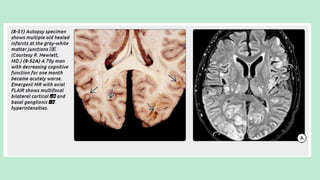

MULTIPLE EMBOLIC INFARCTS

The differentials of multiple embolic infarcts are:

1. Cardio-embolic infarcts.

2. Fat embolism.

3. Gas embolism.

FAT EMBOLI

Hypoxia/neurological symptoms with petechial rash

in setting of severely displaced lower extremity

long bone fractures (most commonly femoral

neck fractures)

The term "cerebral fat emboli" (CFE) refers

to the neurologic manifestations of FES.

Etiology:

Small vessel occlusion from

fat particles

Inflammatory changes in

surrounding tissue initiated

by breakdown of fat into free

fatty acids and other

metabolic byproducts.

CEREBRAL FAT EMBOLI (FES)

Hallmarks is:

Arteriolar fat emboli with perivascular

microhemorrhages.

Imaging findings reflect the effects of the fat

emboli (i.e., multifocal tiny strokes and

microhemorrhages) on brain tissue, not the

fat itself.

NECT scan: Generally normal

MRI: MR shows numerous (average = 50) punctate or confluent

hyperintensities in the cerebellum, basal ganglia, periventricularWM, and GM-

WM junctions on T2/FLAIR.

DWI shows innumerable tiny punctate foci of diffusion restriction in multiple

vascular distributions, the "star field“ pattern.

The deep watershed border zones are commonly involved.

Solitary or multiple small hypointense "blooming" foci can be identified in up

to one-third of all FES cases onT2* GRE. SWI discloses innumerable (>200)

tiny "black dots" in the majority of patients.